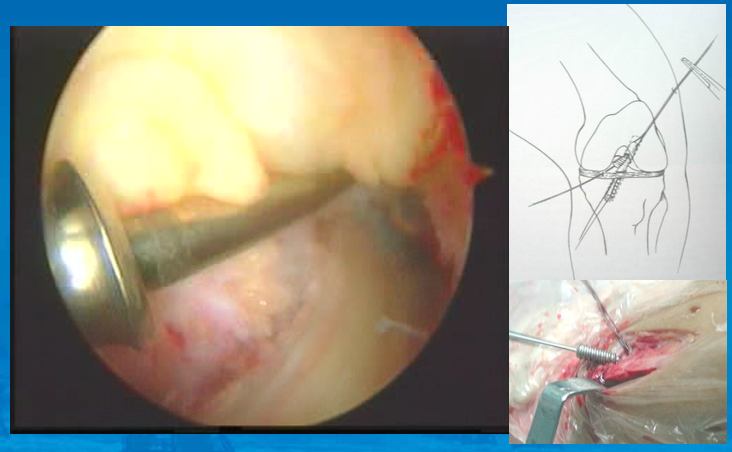

外科技术采用三切口入路:前外,前内和内侧辅助入路。AM和PL的分界可见一个骨嵴

辅助内侧入路钻PL股骨隧道

屈曲90 °,导针在前侧关节软骨边缘后方5-7MM,上方3MM进入,屈曲110 °钻隧道。用直径6或7MM的钻头。

胫骨隧道:PL在55 ° AM在45 °在胫骨皮质上,PL入点位于AM入点的远端后内侧。PCL,外侧半月板根部和AM的止点构成三角,PL位于距其后角大约3-5MM,探针是单束重建的位置。

AM股骨隧道:在PL后侧边缘后方大约2MM,可以由胫骨隧道建立,直径一般7-8MM。

穿胫骨隧道可能有半数患者不能得到正确的隧道位置,这是可以用辅助入路。

植入:先PL后AM